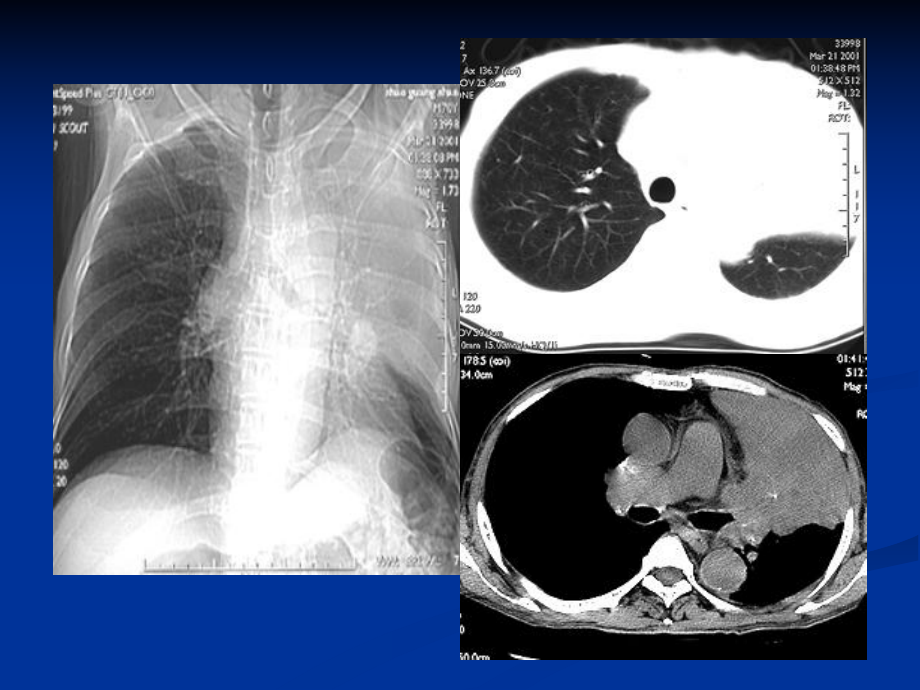

肺部疾病基本征象及分析肺部疾病基本征象及分析 CT值:-58HU恶性肿块恶性肿块支气管胸膜瘘合并脓胸